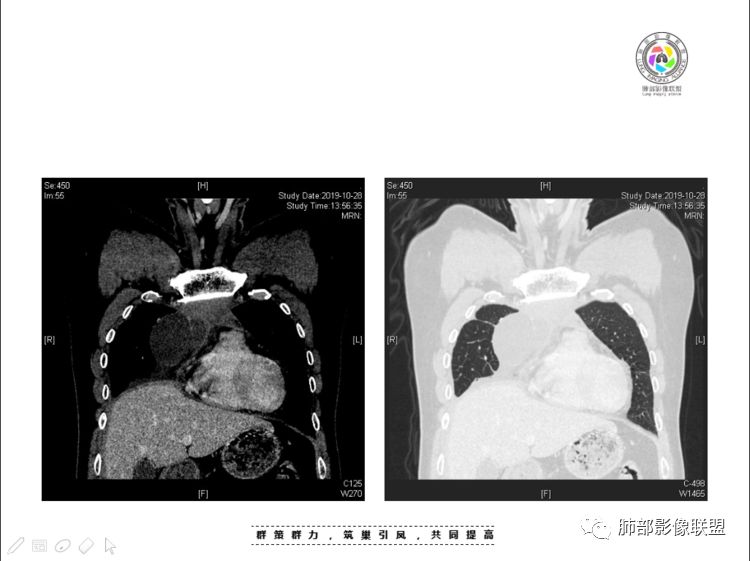

南边:大家看看前纵隔的病灶,符合肿瘤吗脂肪,周围密度增高

三个石头:比较散;像炎症的蔓延生长南边:是,这些看着心里不踏实觉得把这个纳入肿瘤去考虑是否合适总觉得边缘收缩的、散在的朝周围蔓延;中央还跨过脂肪,朝对侧胸膜蔓延把这个与囊性病变连到一起去考虑是否还需要斟酌一下因为这个就方向差异大了南边:连在一起,囊实性,边界不清,自然考虑恶性:如果独立,囊张力高、边界清楚,间隔,自然朝良性考虑:

我认为囊张力高,积液中的气体均在周围,外侧、下方,囊内有间隔:各腔密度不一致;提示:囊腔属于前纵隔,不是包裹性积液;现在的问题:囊腔与内侧的病灶是否是一体的

南边:我总觉得这个纵隔内不像是一个肿块的改变,扁平,周围蔓延:有符合炎性的的特点,或者肿瘤的侵犯;但是肿瘤的侵犯,不大符合,实性部位的边缘过于柔和,没有毛糙的侵犯边缘。

2、前纵隔内病灶囊实性混杂密度病灶,囊性病灶主要位于右侧,张力较高,有分隔影,囊壁右侧缘光整,病灶左侧实性部分边界不清明显强化,病灶肺瘤交界面大部分边界清楚,部分模糊。